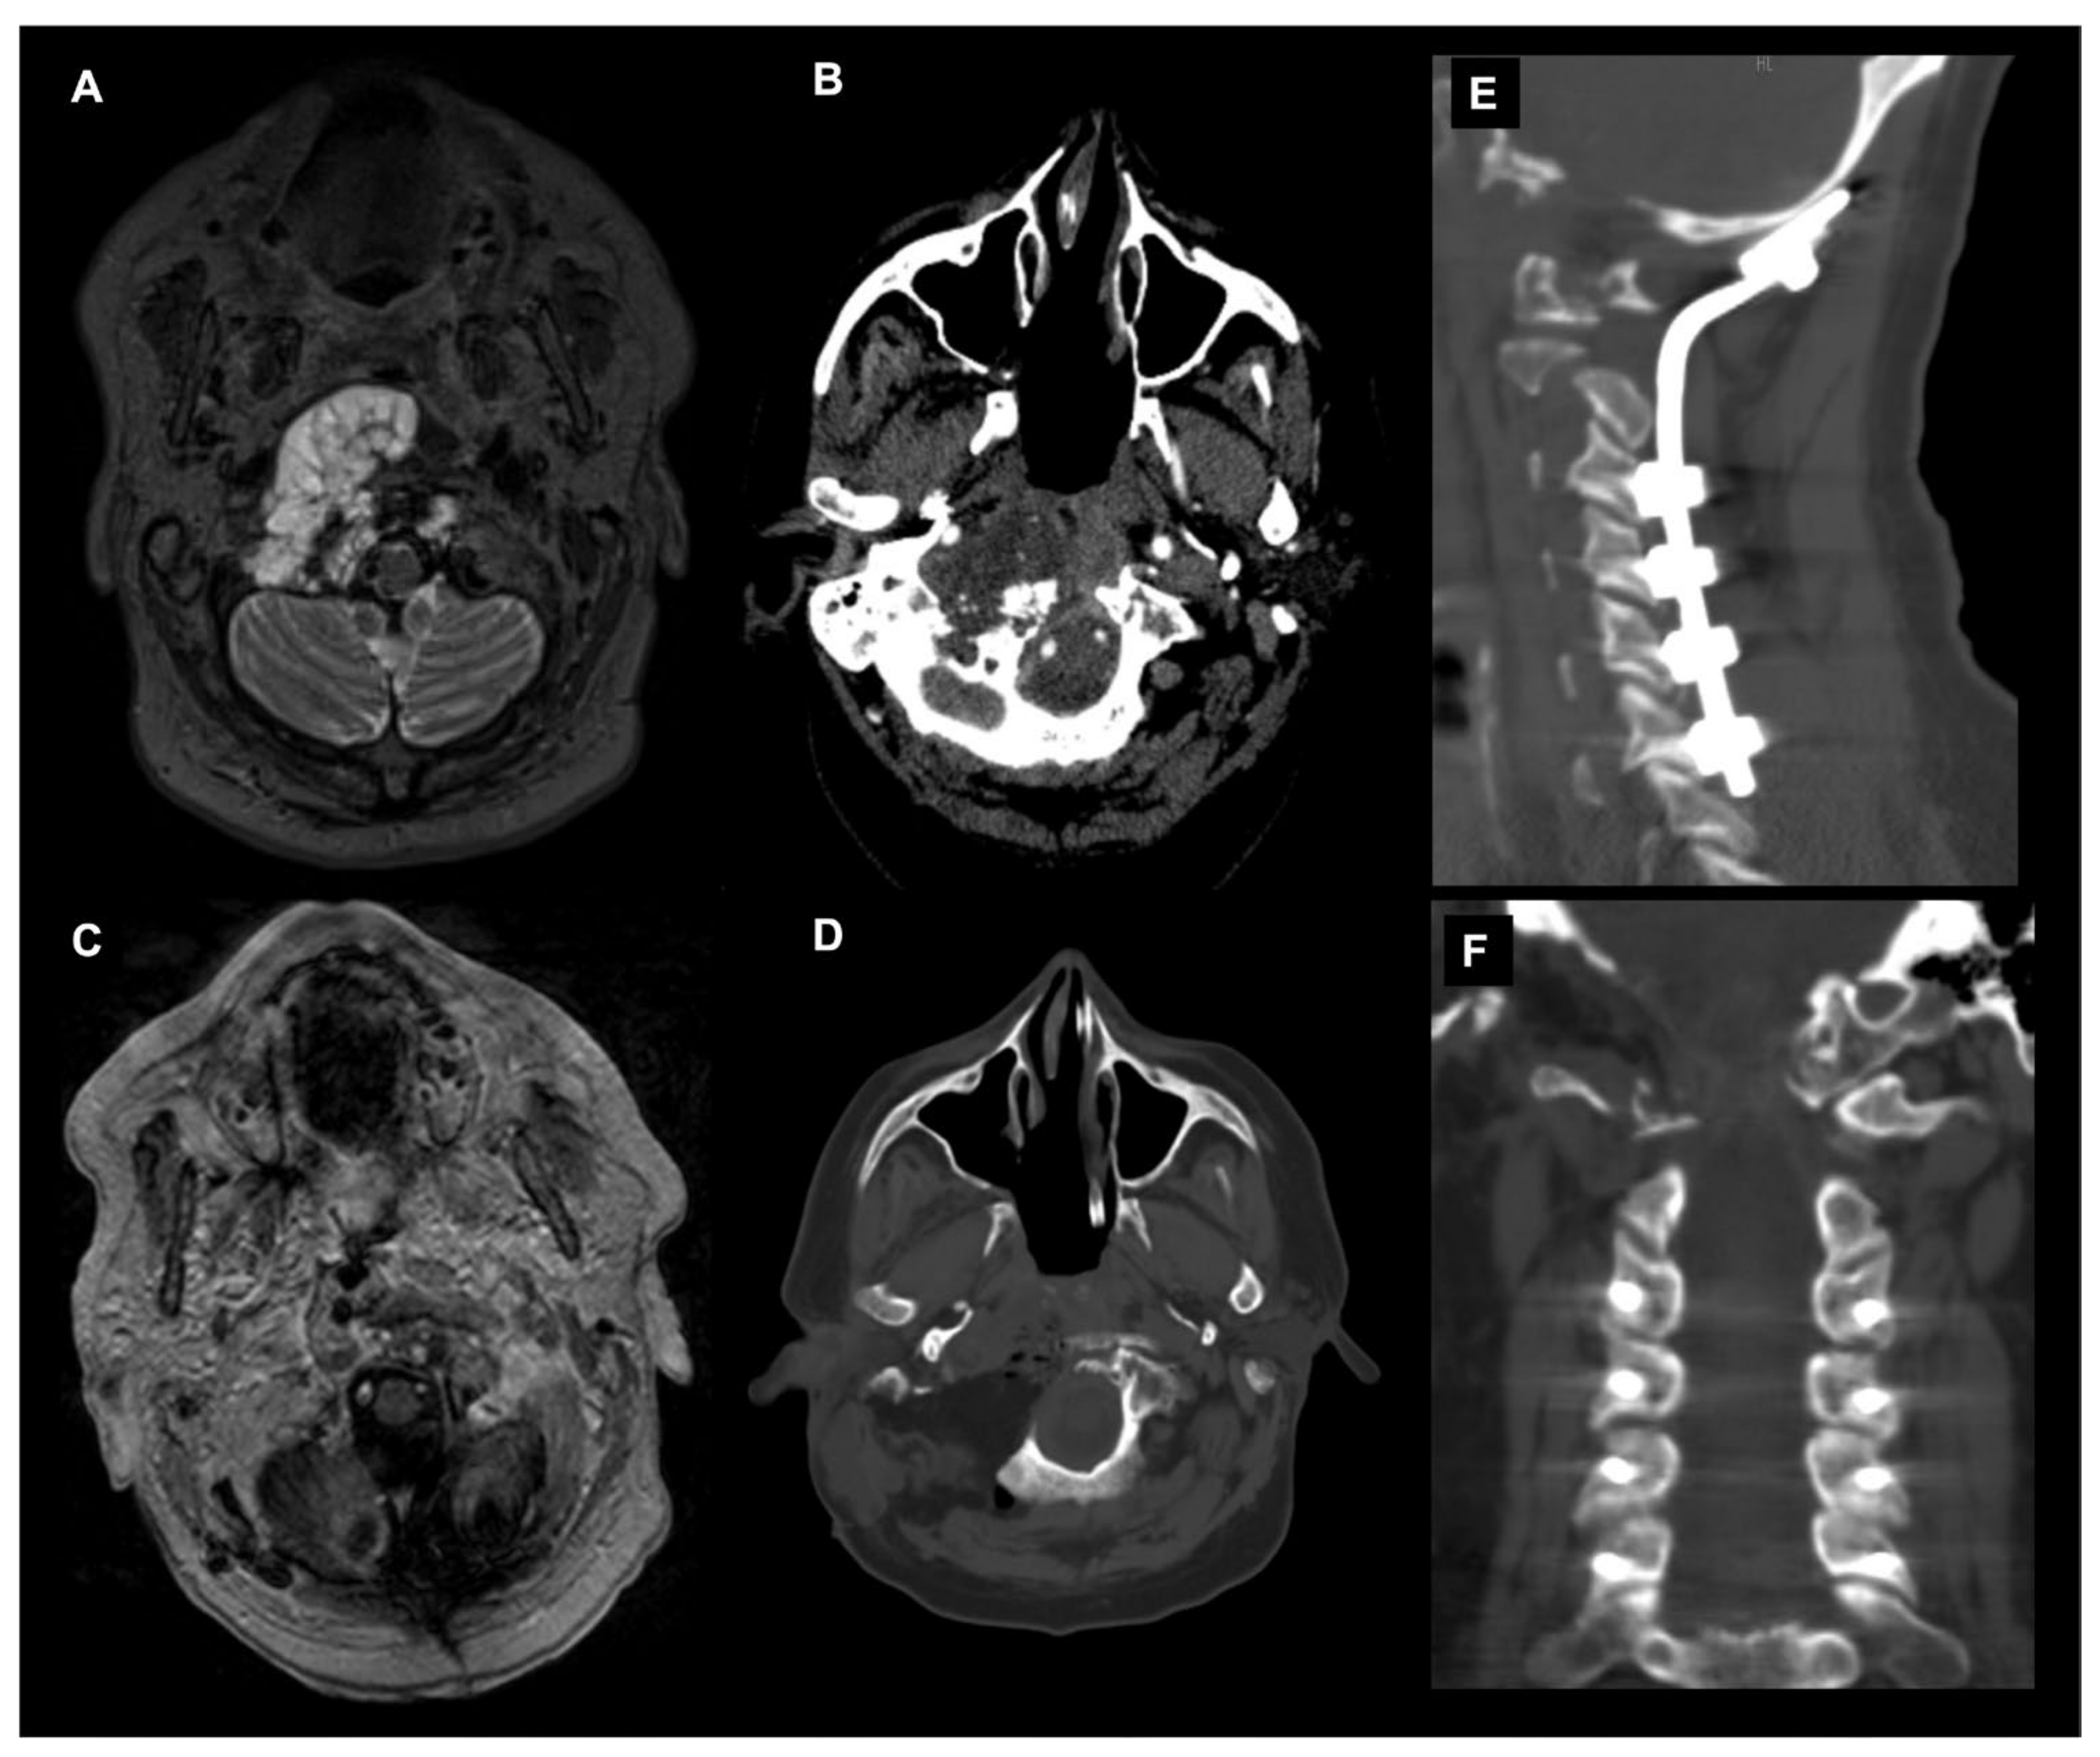

The posterior and posterolateral approaches represent two further operative techniques for the treatment of CVJ primary and metastatic neoplastic diseases available in the neurosurgical armamentarium (Figure 6).

Figure 6.

Combined endoscopic endonasal approach and far-lateral transcondylar and petro-occipital trans-sigmoid approach to recurrent CVJ chordoma and subsequent occipitocervical fixation. Axial T2-weighted MR image (A) and angio CT scan (B) showing a recurrent predominantly right craniovertebral junction chordoma. The chordoma infiltrates the rhinopharynx, C0-C1-C2 joint complex and the entire right occipital condyle. A combined endoscopic endonasal approach associated with far-lateral transcondylar and petro-occipital trans-sigmoid approach has been performed. (C) Axial postoperative T1-weighted after contrast injection image and (D) noncontrast CT scan disclosed a gross total resection with the destruction of the right clival–atlo–axial joint. An occipital-cervical fixation was therefore postoperatively planned and performed (E,F).

The main variables determining the selection of the surgical approach are related to the tumor pathology, i.e., primary vs metastatic disease; anatomy, i.e., tumor location and involvement of the adjacent structures; and biomechanical considerations.

In the subsequent paragraph, we will briefly discuss the oncological and anatomical concepts guiding the selection of the posterior and posterolateral approach around the CVJ followed by a dedicated focus on the treatment of CVJ instability related to the aforementioned surgical approaches.